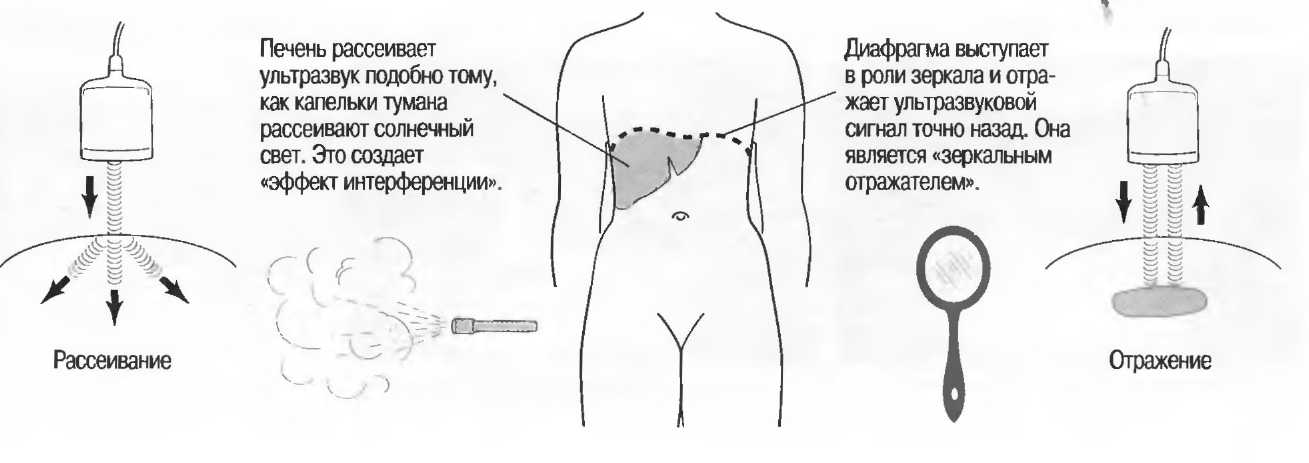

Ткани тела отражают ультразвук двумя способами. Некоторые ткани выступают в роли зеркала, отражая волны точно назад. Другие рассеивают ультразвуковые волны подобно капелькам тумана, рассеивающим световой поток. Например, диафрагма является «зеркалом», по технической терминологии — «зеркальным отражателем». На экране монитора появится четкое и точное изображение, хорошо соответствующее положению и форме диафрагмы. Печень же рассеивает ультразвуковую волну, и положение отраженных сигналов на экране не соответствует в точности отраженным структурам в печени. Это и есть явление интерференции, имеющей место в результате рассеивания сигналов в различных направлениях. В любом случае использование черного фона с белыми сигналами позволяет лучше дифференцировать структуры.

Если отражающая граница значительно больше, чем длина волны (в 10 или 20 раз), она становится зеркалом и называется зеркальным отражателем.

Череп плода, дифрагма, стенки сосудов, соединительная ткань являются примерами зеркальных отражателей (рис. 6).

Печень и почечная паренхима являются примером рассеивающей среды.

Рис.6. Сагиттальный срез печени: имеется очень сильное (зеркальное) отражение от диафрагмы, являющейся таким мощным отражателем, что изображение печени повторяется за ней. Ультразвуковые волны проходят через печень после излучения, затем повторно — после отражения от диафрагмы, затем — от поверхностей тканевых структур.

Рассеивание |

Отражение и преломление ультразвуковых волн сразу во многих направлениях. Это наблюдается в случае, если отражающий объект меньше длины ультразвуковой волны. В этом случае только небольшая часть передаваемой энергии возвращается в трансдьюсер. |

Зеркальный отражатель |

Отражающая структура с гладкой поверхностью, большая по размерам, чем длина ультразвуковой волны, например стенки сосудов или тканевые пере- городки. В зависимости от угла падения ультразвукового луча может происходить полное или частичное отражение. |

Эффект зеркала |

Отражение всех или почти всех ультразвуковых волн некоторыми тканями или границами раздела сред. например границей «диафрагма-легкие». Эффект зеркала иногда создает артефакт зеркального отражения, дающий удвоение изображения. |